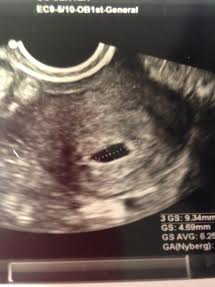

Beta #1 12dpo - 164 & progesterone - 89!, Beta #2 16 dpo - 1189, 5w3d - u/s shows TWINS!

6/19- u/s showed heartbeats! Baby A 111 & Baby B 118, both measuring 6w1d